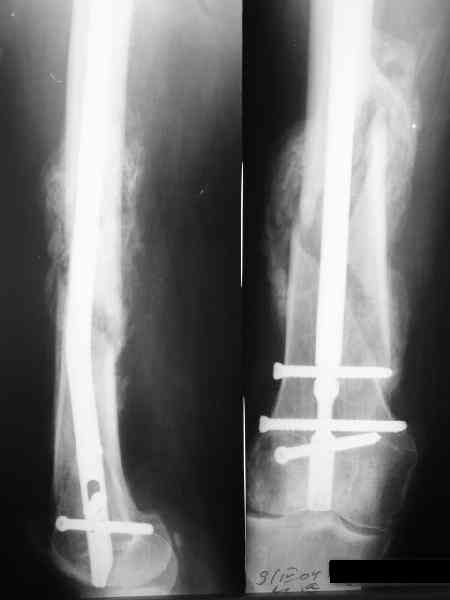

В приложении как раз видна эволюция использововшихся у нас большеберцовых гвоздей. Первый - дизайн как у UTN, второй - разнесены 45 градусные отверстия (зачем их вообще изначально так нелепо на одном уровне сделалм???), третий - убрано сиавшее лишним статическое отверстие, Herzog's bend перемещен более проксимально.

Насколько я помню, мы использовали этот вариант после знакомства с гвоздями SIGN, которые вообще одинаковые для бедра и голени, и дизайн у них большеберцовый.